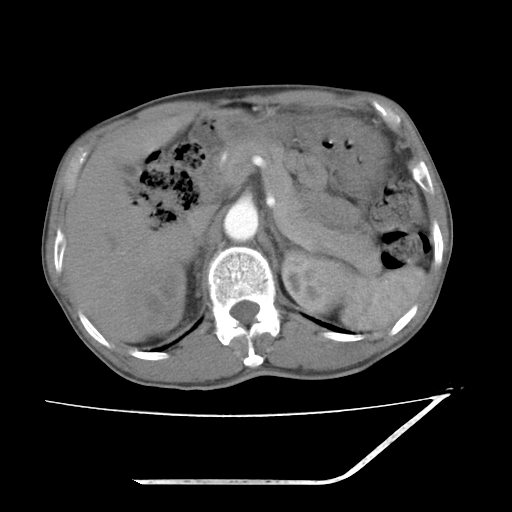

增强

考虑右肾盂癌,肾动脉受侵,右肾功能减退,右肾盂输尿管积水,管壁增厚,考虑种植转移,应该把下面扫完的

支持右侧肾盂癌伴肾静脉瘤栓形成可能性大,右肾结石.肝右叶后段低密度影,不除外转移.

考虑右侧肾盂癌。右侧输尿管扩张未扫描完。

右肾盂癌,肾动脉受侵,右肾盂输尿管积水,管壁增厚,考虑种植转移

右肾盂移行细胞癌并右输尿管中段转移.肾积水.

1.右侧肾盂癌伴肾盂积水。

2.肾脏功能减退,原因有:(1)肾动脉受侵。(2)肾静脉受侵(3)肾积水,等。本例,肾动脉显影较好,但受压明显;肾静脉无明显显示,受压或静脉癌栓,下腔静脉腔内未见明显充盈缺损。

3.右侧上段输尿管扩张,原因:(1)积水所致;(2)种植。